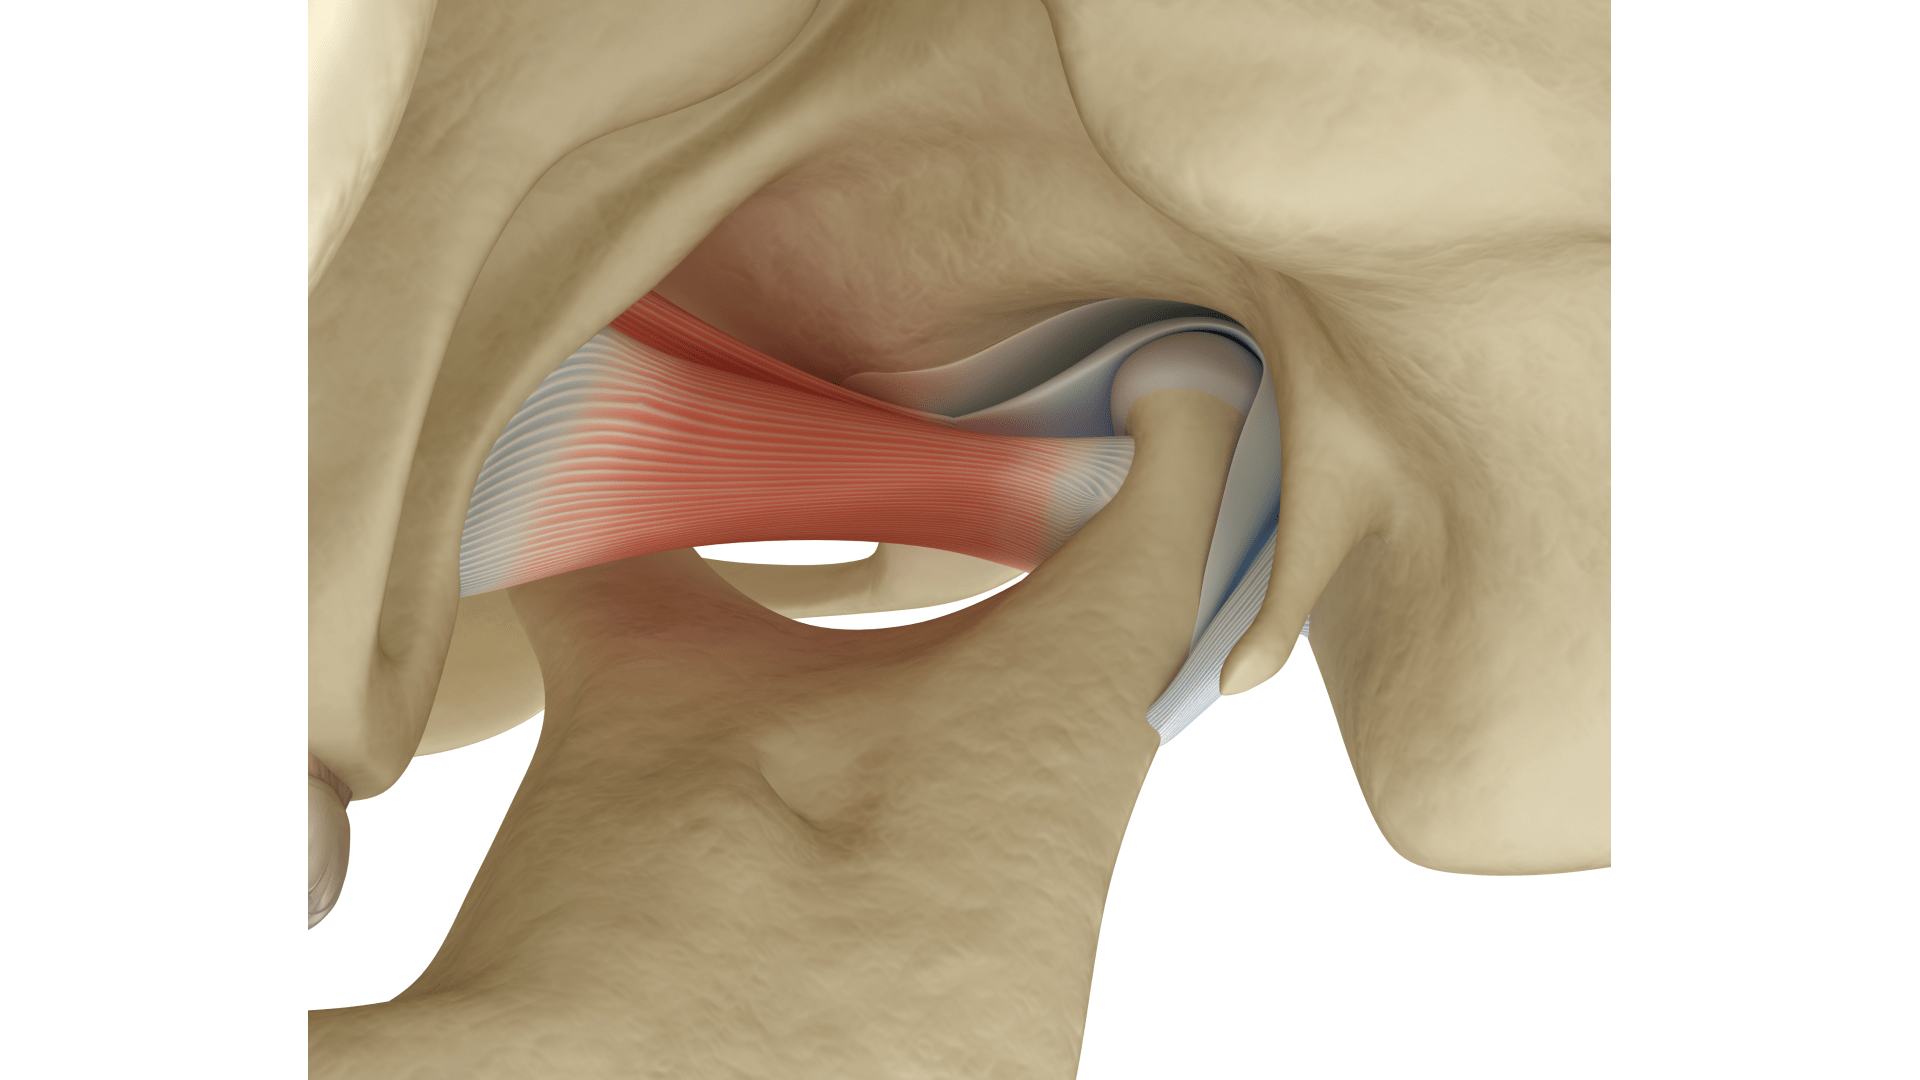

Скронево-нижньощелепний суглоб (СНЩС) — це парний суглоб, що з’єднує нижню щелепу зі скроневою кісткою черепа. Він є одним із найскладніших в організмі людини, адже може виконувати широкий діапазон рухів — відкривання, висування, обертання та зміщення щелепи вбік. Завдяки цьому ми можемо жувати, говорити, ковтати й навіть виражати емоції через міміку.

СНЩС має складну анатомію. Він складається з:

- суглобової головки нижньої щелепи;

- суглобової ямки;

- міжсуглобового диска;

- суглобової капсули та зв’язок;

- м’язів (скроневого, жувального, крилоподібних).

Основна функція СНЩС полягає у рухливості нижньої щелепи під час жування, мовлення та ковтання. Крім того, суглоб виконує амортизаційну роль. Хрящовий диск і капсула пом’якшують тиск і захищають кісткові структури від перевантаження.